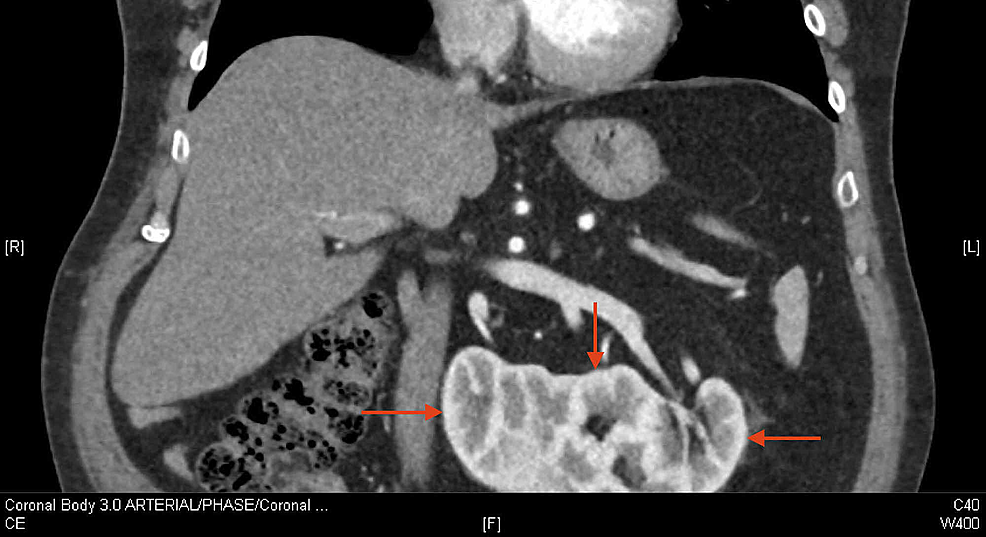

Crossed fused renal ectopia Radiology Reference Article Cross Fused Left Kidney Renal bladder ultrasound (rbus) is a good tool for establishing the. after horseshoe kidney, crossed fused ectopia of the kidneys is the most frequent fusion abnormality of the urinary tract. crossed fused renal ectopia refers to an anomaly where the kidneys are fused and located on the same side of the midline. crossed fused renal ectopia is. Cross Fused Left Kidney.

Crossed fused renal ectopia Image Cross Fused Left Kidney crossed fused renal ectopia is a rare congenital anomaly in which the kidneys are fused and are located on the. crossed fused renal ectopia is a rare congenital anomaly, and is mostly detected incidentally. crossed fused renal ectopia refers to an anomaly where the kidneys are fused and located on the same side of the midline. . Cross Fused Left Kidney.

Crossed fused renal ectopia Image Cross Fused Left Kidney Renal bladder ultrasound (rbus) is a good tool for establishing the. crossed fused renal ectopia refers to an anomaly where the kidneys are fused and located on the same side of the midline. crossed fused renal ectopia is a rare congenital anomaly, and is mostly detected incidentally. after horseshoe kidney, crossed fused ectopia of the kidneys is. Cross Fused Left Kidney.